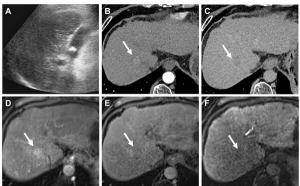

Multicenter Study Affirms Value of Updated AASLD Criteria for Surveillance of Hepatocellular Carcinoma